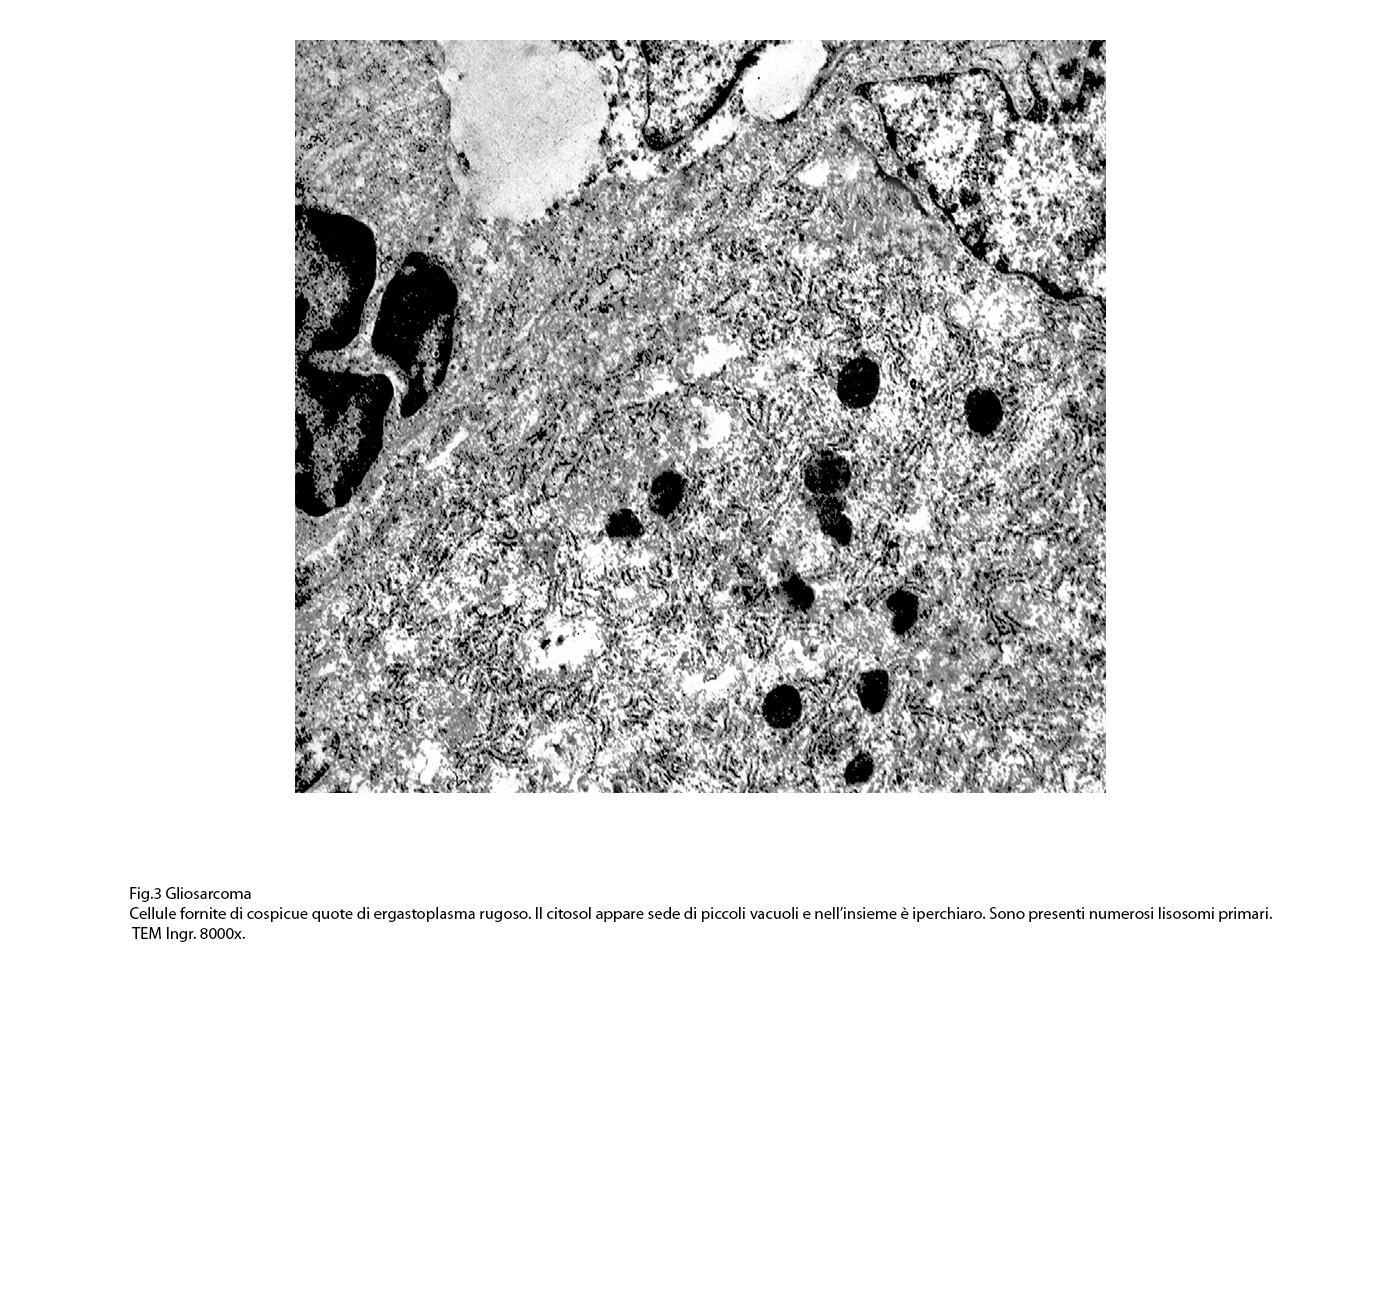

Fig.3